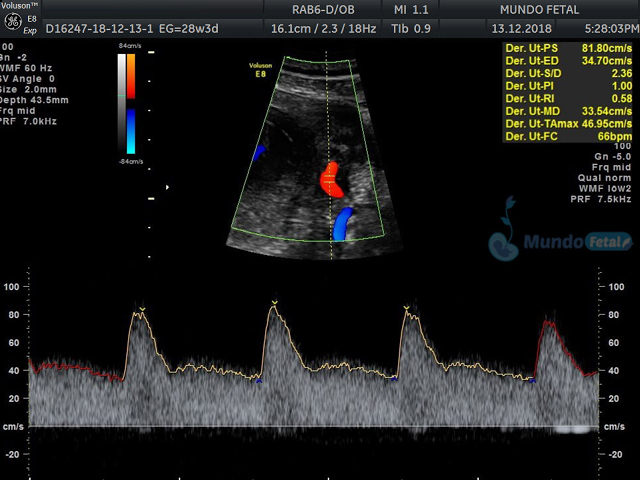

Se recomienda de 32-34 semanas, realizando valoración de crecimiento armónico (4 medidas específicas), valoración anatómica, líquido amniótico, flujos sanguíneos fetales y placentarios perfilando el bienestar fetal hacia el final de embarazo.